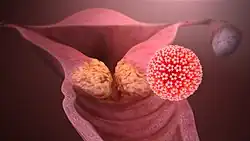

Viral infection is a major risk factor for cervical and liver cancer.[74] A virus that can cause cancer is called an oncovirus. These include human papillomavirus (cervical carcinoma), Epstein–Barr virus (B-cell lymphoproliferative disease and nasopharyngeal carcinoma), Kaposi's sarcoma herpesvirus (Kaposi's sarcoma and primary effusion lymphomas), hepatitis B and hepatitis C viruses (hepatocellular carcinoma), and Human T-cell leukemia virus-1 (T-cell leukemias).

In Western developed countries, human papillomavirus (HPV), hepatitis B virus (HBV) and hepatitis C virus (HCV) are the most common oncoviruses.[75] In the United States, HPV causes most cervical cancers, as well as some cancers of the vagina, vulva, penis, anus, rectum, throat, tongue and tonsils.[76] Among high-risk HPV viruses, the HPV E6 and E7 oncoproteins inactivate tumor suppressor genes when infecting cells. In addition, the oncoproteins independently induce genomic instability in normal human cells, leading to an increased risk of cancer development.[77] Individuals with chronic hepatitis B virus infection are more than 200 times more likely to develop liver cancer than uninfected individuals.[78] Liver cirrhosis, whether from chronic viral hepatitis infection or excessive alcohol use, is independently associated with the development of liver cancer, but the combination of cirrhosis and viral hepatitis presents the highest risk of liver cancer development.[78]